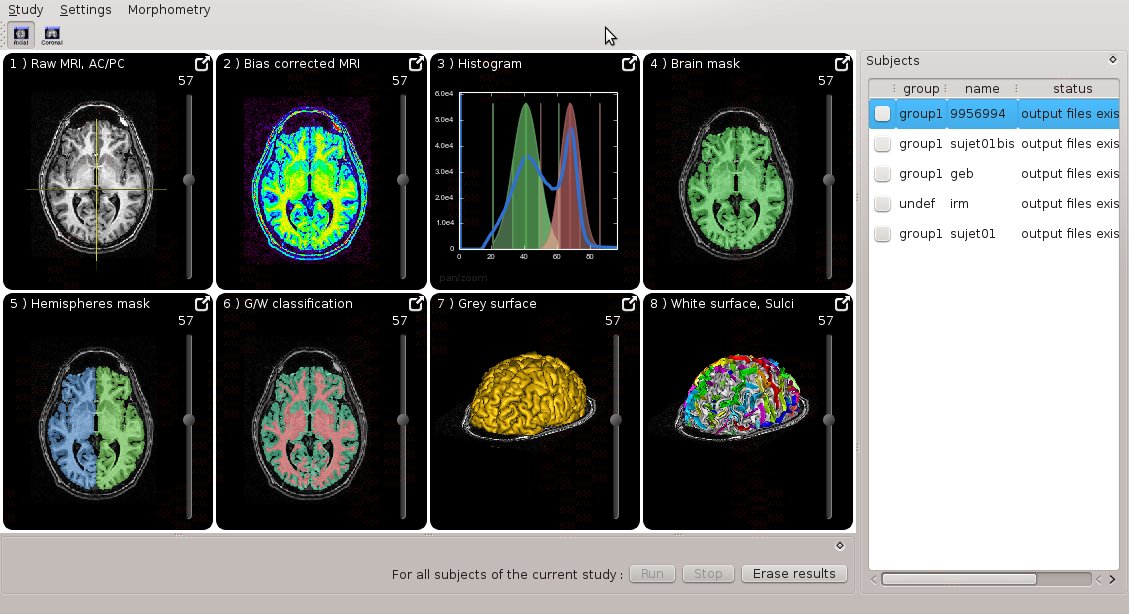

Morphologist UI

Morphologist now has a new graphical interface, featuring simplified user experience and quick interactive visualization:

Docmentation can be found here

It can be run either as a standalone program (morphologist), or through BrainVISA.